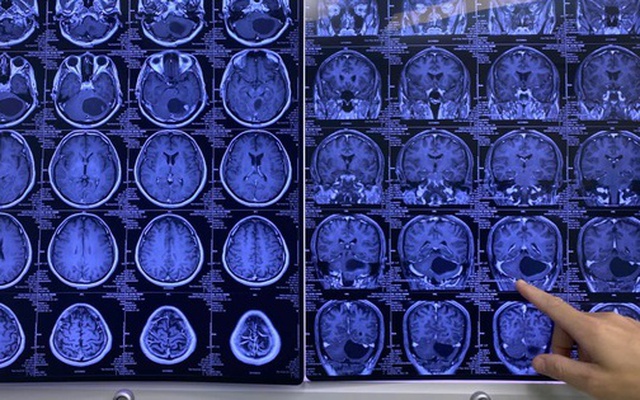

Ảnh chụp khối u to bằng quả trứng vịt của bệnh nhân

Theo BSCKII Đỗ Văn Long, Bệnh viện Đa khoa Quốc tế Minh Anh (người trực tiếp mổ), tiểu não vốn nhỏ bé nhưng ở bệnh nhân này lại chứa một khối u to bằng quả trứng vịt, chèn ép trực tiếp vào thân não – nơi điều khiển mọi hoạt động sống còn của cơ thể. Chỉ cần một tích tắc sơ sẩy hoặc khối u lớn thêm chút nữa, bệnh nhân có thể tử vong đột ngột.